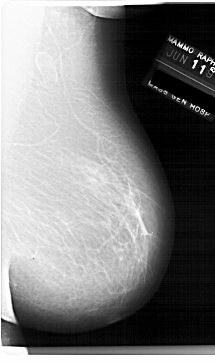

A_1920_1.RIGHT_MLO

RIGHT_MLO LINES 6871 PIXELS_PER_LINE 4081 BITS_PER_PIXEL 12 RESOLUTION 43.5 NON_OVERLAY

ABNORMALITY 2

LESION_TYPE MASS SHAPE OVAL MARGINS OBSCURED

ASSESSMENT 3

SUBTLETY 4

PATHOLOGY BENIGN

TOTAL_OUTLINES 1

BOUNDARY